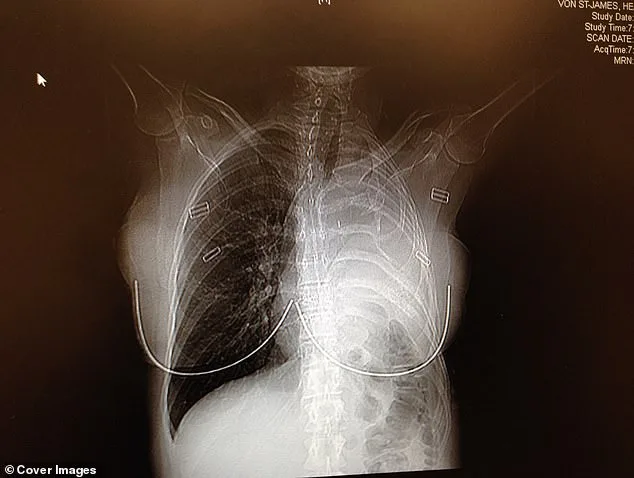

A CT scan revealed a tumor in the pleura, the thin tissue lining the lungs and chest cavity. She was diagnosed with malignant pleural mesothelioma, a rare and aggressive cancer with a grim prognosis. "I didn't know what mesothelioma was," Von St James recalled. Her doctor's question—"Have you or anyone in your family ever worked with asbestos?"—pierced the silence. Her husband's reply, "Oh this is bad," confirmed her worst fears. Without prompt treatment, her survival outlook was bleak: 15 months at most. The diagnosis upended her world.

Thinking of her newborn, Von St James threw herself into treatment. 'There was no question that I was going to die,' she said. 'It was like, what do I do to beat this?' The words hang heavy, a testament to the despair that often accompanies a mesothelioma diagnosis. She and her husband flew to Boston to see a specialist who performed a radical surgery. In February 2006, doctors removed her left lung, a rib, the lining of her heart, and part of her diaphragm, replacing them with surgical Gore-Tex. The tumor was excised with clean margins. No visible cancer remained.

In February 2006, doctors removed her left lung, the rib above it, the lining of her heart, and part of her diaphragm. In their place, they used surgical Gore-Tex—the same material used in waterproof clothing—to rebuild parts of her chest. The surgery was a success. Surgeons had excised the tumor with perfect margins, leaving no visible cancer behind. As a precaution, to make sure they removed every bit of cancer, doctors infused warm drugs directly into her chest cavity, rocking her back and forth for an hour to circulate the medicine and kill any remaining cancer cells. 'Patients call it the "shake and bake,"' Von St James said.